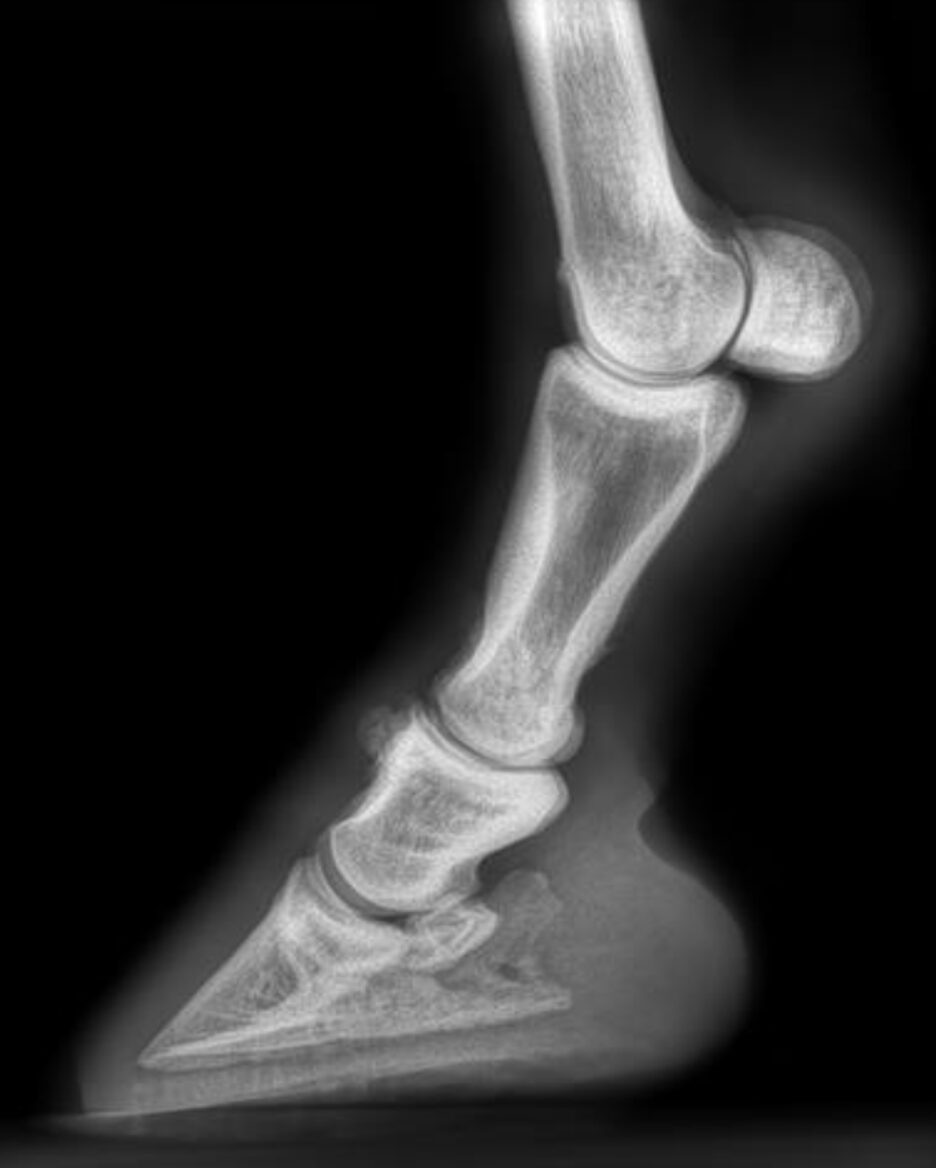

On examination, Levi showed a Grade 2/5 lameness in the left forelimb, most evident when lunged to the left on a hard surface. Mild to moderate swelling was noted around the left proximal interphalangeal joint (pastern) joint, along with a mild reaction to flexion. The horse’s conformation was within normal limits.

To localize the source of pain, intra-articular analgesia was administered into the left proximal interphalangeal joint. This resulted in complete resolution of the lameness, confirming the pastern joint as the primary source. Radiographs of both distal forelimbs revealed moderate osteoarthritis.